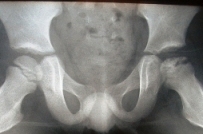

Puis la maladie évolue ensuite en quatre étapes radiologiques :

• Image d'un décollement sous-chondral (petite lacune) ;

• densification du noyau épiphysaire suivant sa fragmentation ;

• reconstruction articulaire avec réossification ;

• déformation en coxa plana.

Une image radiographique pathologique suffit au diagnostic.